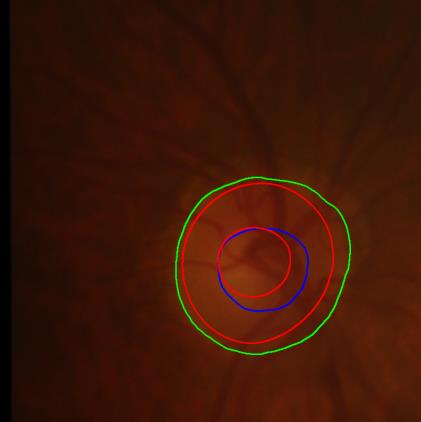

Modern deep neural networks struggle to transfer knowledge and generalize across diverse domains when deployed to real-world applications. Currently, domain generalization (DG) is introduced to learn a universal representation from multiple domains to improve the network generalization ability on unseen domains. However, previous DG methods only focus on the data-level consistency scheme without considering the synergistic regularization among different consistency schemes. In this paper, we present a novel Hierarchical Consistency framework for Domain Generalization (HCDG) by integrating Extrinsic Consistency and Intrinsic Consistency synergistically. Particularly, for the Extrinsic Consistency, we leverage the knowledge across multiple source domains to enforce data-level consistency. To better enhance such consistency, we design a novel Amplitude Gaussian-mixing strategy into Fourier-based data augmentation called DomainUp. For the Intrinsic Consistency, we perform task-level consistency for the same instance under the dual-task scenario. We evaluate the proposed HCDG framework on two medical image segmentation tasks, i.e., optic cup/disc segmentation on fundus images and prostate MRI segmentation. Extensive experimental results manifest the effectiveness and versatility of our HCDG framework.